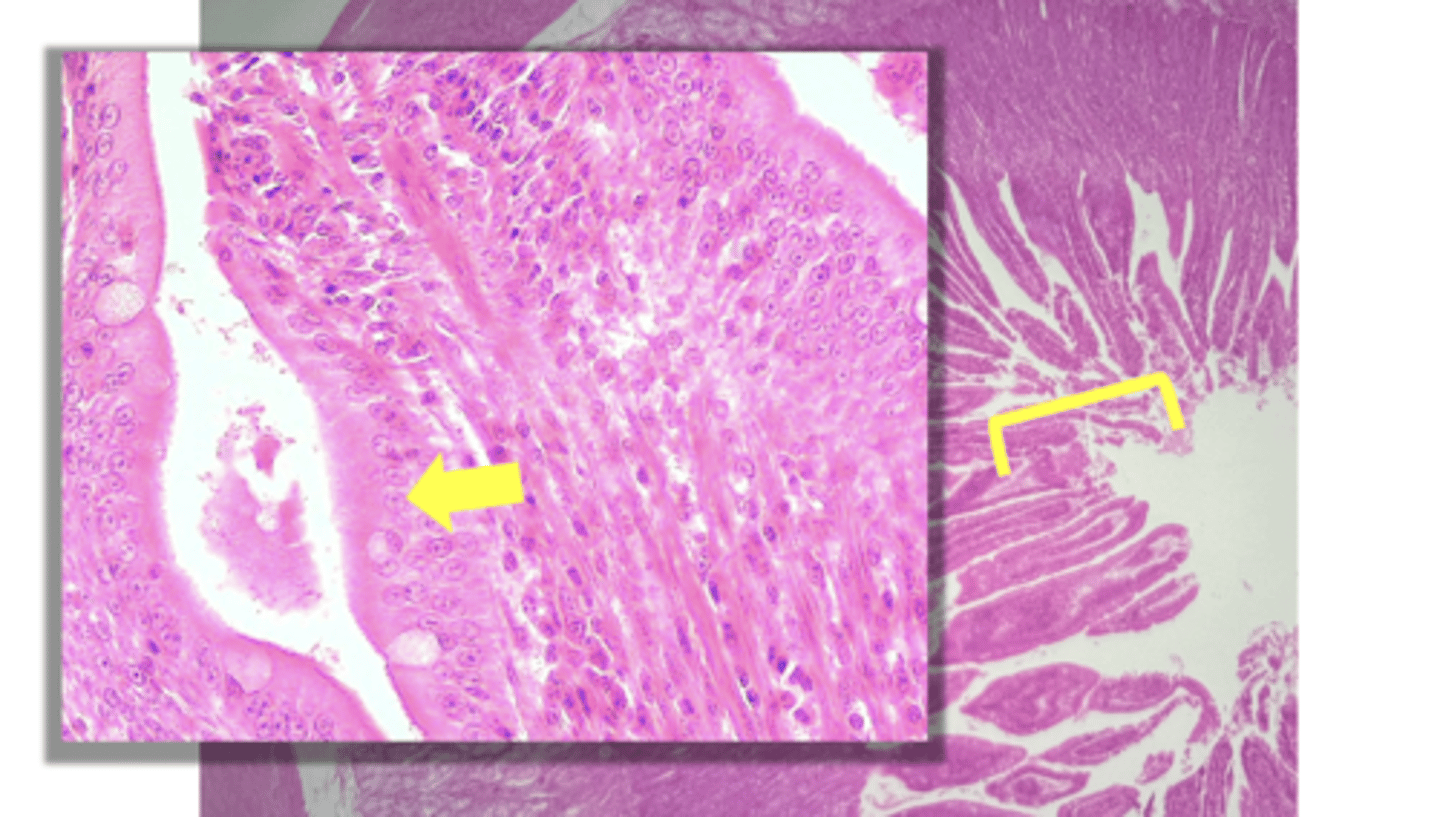

Duodenum (small intestine-cross section)

name the tissue

Brunner's glands (KEY CHARACTERISTIC)

(duodenum)

Villi (KEY CHARACTERISTIC)

simple columnar epithelium

type of cell

intestinal crypts